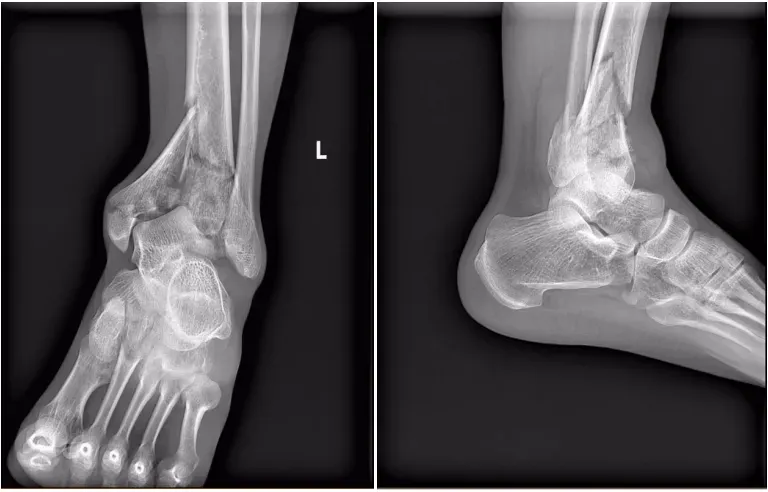

患者被送至医院时,查体见左踝关节严重畸形伴皮肤张力性水疱,足背动脉搏动减弱。医疗团队第一时间为患者安排患肢CT检查,影像结果令人揪心:胫骨远端粉碎性骨折,内踝垂直劈裂骨折,后踝关节面受累骨折,踝关节完全脱位。结合影像学表现与临床症状,确诊为AO/OTA43-C3型Pilon骨折——这是骨科领域公认的“关节骨折治疗天花板”,不仅骨折结构复杂,还伴随软组织高危损伤,稍有延误或处置不当,就可能导致肢体功能障碍甚至截肢风险。